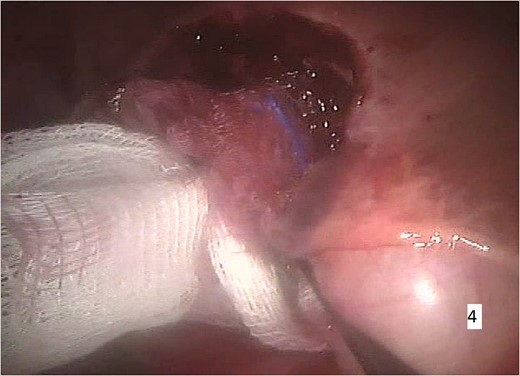

The procedure was carried out under general anaesthesia and the patient was monitored by ECG. Peripheral oxygen saturation (SpO2), end-tidal CO2 concentration and body temperature were measured throughout the whole operation. Gastric intubation and bladder catheterization were realized. A central venous line was placed and an intra-arterial catheter was positioned for continuous monitoring of the blood pressure and gas analysis. The patient was placed in supine position with parted legs in 20° Trendelenburg position. Pneumoperitoneum was achieved. A port was placed for the robotic camera and three additional ports were introduced. Cholecystectomy was first performed leading to a better optimal exposure of the hepatic hilum. Using the da Vinci surgical system, a right segmental hepatectomy was performed (Figs 3 and 4).

Intraoperative imaging. Segmental right hepatectomy and removal of the excised specimen through a small abdominal incision.